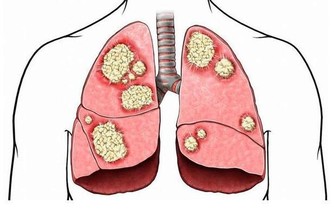

這可能也是受到了真菌感染,但除此外反應性關節炎和肺部疾病也會有如此症狀。若你患上皮膚病如濕疹和乾癬,你也會有微黃色、生長緩慢的粗厚指甲。另外一種可能性,是源自於不良的血液循環,比如糖尿病會讓手指和腳趾的血液流動緩慢,而影響了皮膚的品質。

亦稱作鼓棰指,即手指末端增生、肥厚,這可能是完全無害或源自遺傳,但如果是指甲突然開始軟化並大小不一,那代表你血液裡的含氧量低。此外,杵狀指甲有可能是肺部肝臟疾病、心臟病和炎症性腸疾病而引起的。